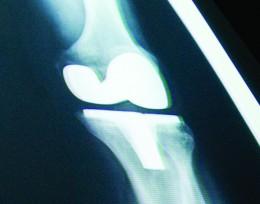

Wright State Physicians Orthopaedics will offer an educational session, “Total Knee Arthroplasty — Facts and Myths,” on Tuesday, Jan. 20, at 7 p.m., in Classroom 1 on the second floor of the Wright State Physicians Health Center (725 University Blvd.) on the campus of Wright State University. The session is free and open to the public. The speaker is Matthew W. Lawless, M.D., a fellowship-trained orthopaedic surgeon who focuses on knee issues. He is certified by the American Board of Orthopaedic Surgery in the orthopaedic sports medicine subspecialty. Dr. Lawless is an associate professor in the Department of Orthopaedic Surgery, Sports Medicine and Rehabilitation at the Wright State University Boonshoft School of Medicine. He also serves as team physician for Wright State University Athletics. Dr. Lawless will speak about knee arthroplasty, a surgical procedure used to provide relief from knee pain by replacing parts of the knee joint with artificial parts. This is an option used when other treatments — weight loss, medicine, injections or physical therapy — do not work. He will address operative and non-operative treatments for knee pain and their results. He also will discuss the importance of balance and motion. Videos of past sessions may be viewed at www.wrightstatephysicians.org/ortho/video. To register for the session, contact Amy Leach at amy.leach@wrightstatephysicians.org or (937) 208-2128. Wright State Physicians Inc. includes more than 160 physicians affiliated with the Wright State University Boonshoft School of Medicine. The group provides primary and specialty care in a wide range of specialized diagnostic and treatment services throughout the Dayton region.